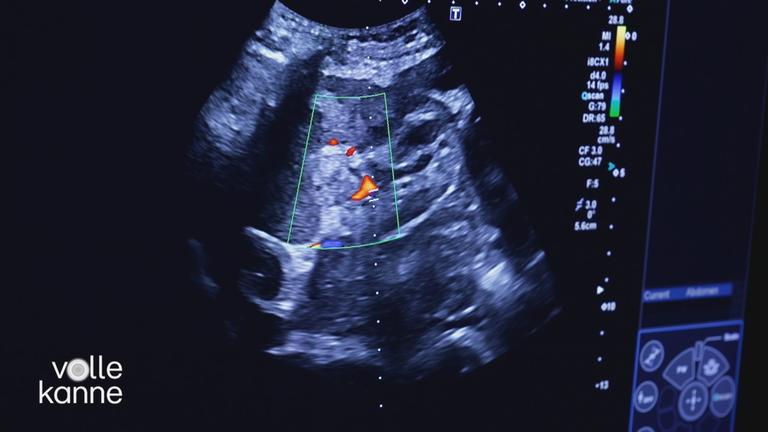

Video5:32Chronische Nierenerkrankung

Video4:54